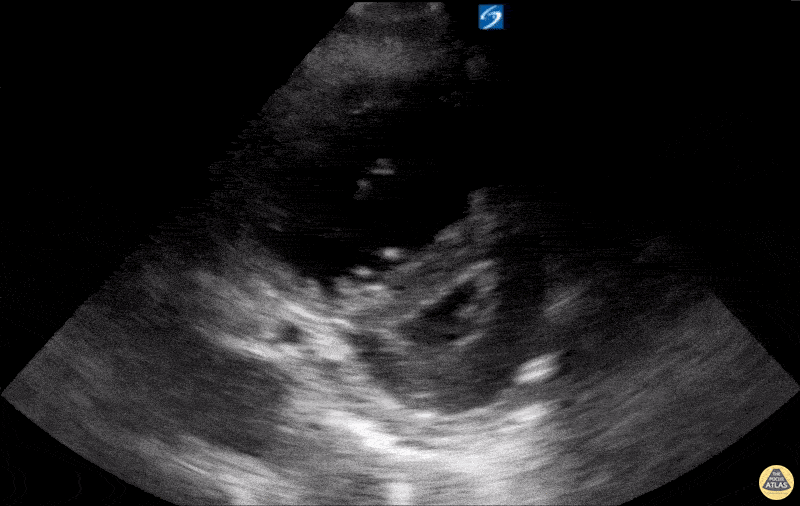

Right Ventricular Dysfunction - RV Strain with RV dilation and D-sign on PSSA

A 74-year-old male patient with Chronic Obstructive Pulmonary Disease (COPD) (not on home oxygen) presented to the ED with acute worsening dyspnea with persistent hypoxia despite supplemental oxygen, tachypnea, and increased work of breathing. There was no infectious or environmental exposure to explain the patient’s presentation. The patient’s differential diagnosis included acute pulmonary embolism (PE) and COPD exacerbation/progression. Parasternal long-axis (PSLA) and short-axis (PSSA) views showed RV dilatation with RV strain. The RV strain was demonstrated by flattening of the interventricular septum, creating a D-shaped LV during systole (D-sign). Also, it shows hyperdynamic LV from tachycardia with near obliteration of the LV cavity in systole. CT angiography scan showed no evidence of PE. The patient was admitted and diagnosed with a progression of severe COPD with pulmonary hypertension and right ventricular remodeling. Contributed by: Hassan Alshaqaq, MBBS, Emergency Medicine Resident at King Saud University Medical City, @HassanAlshaqaq